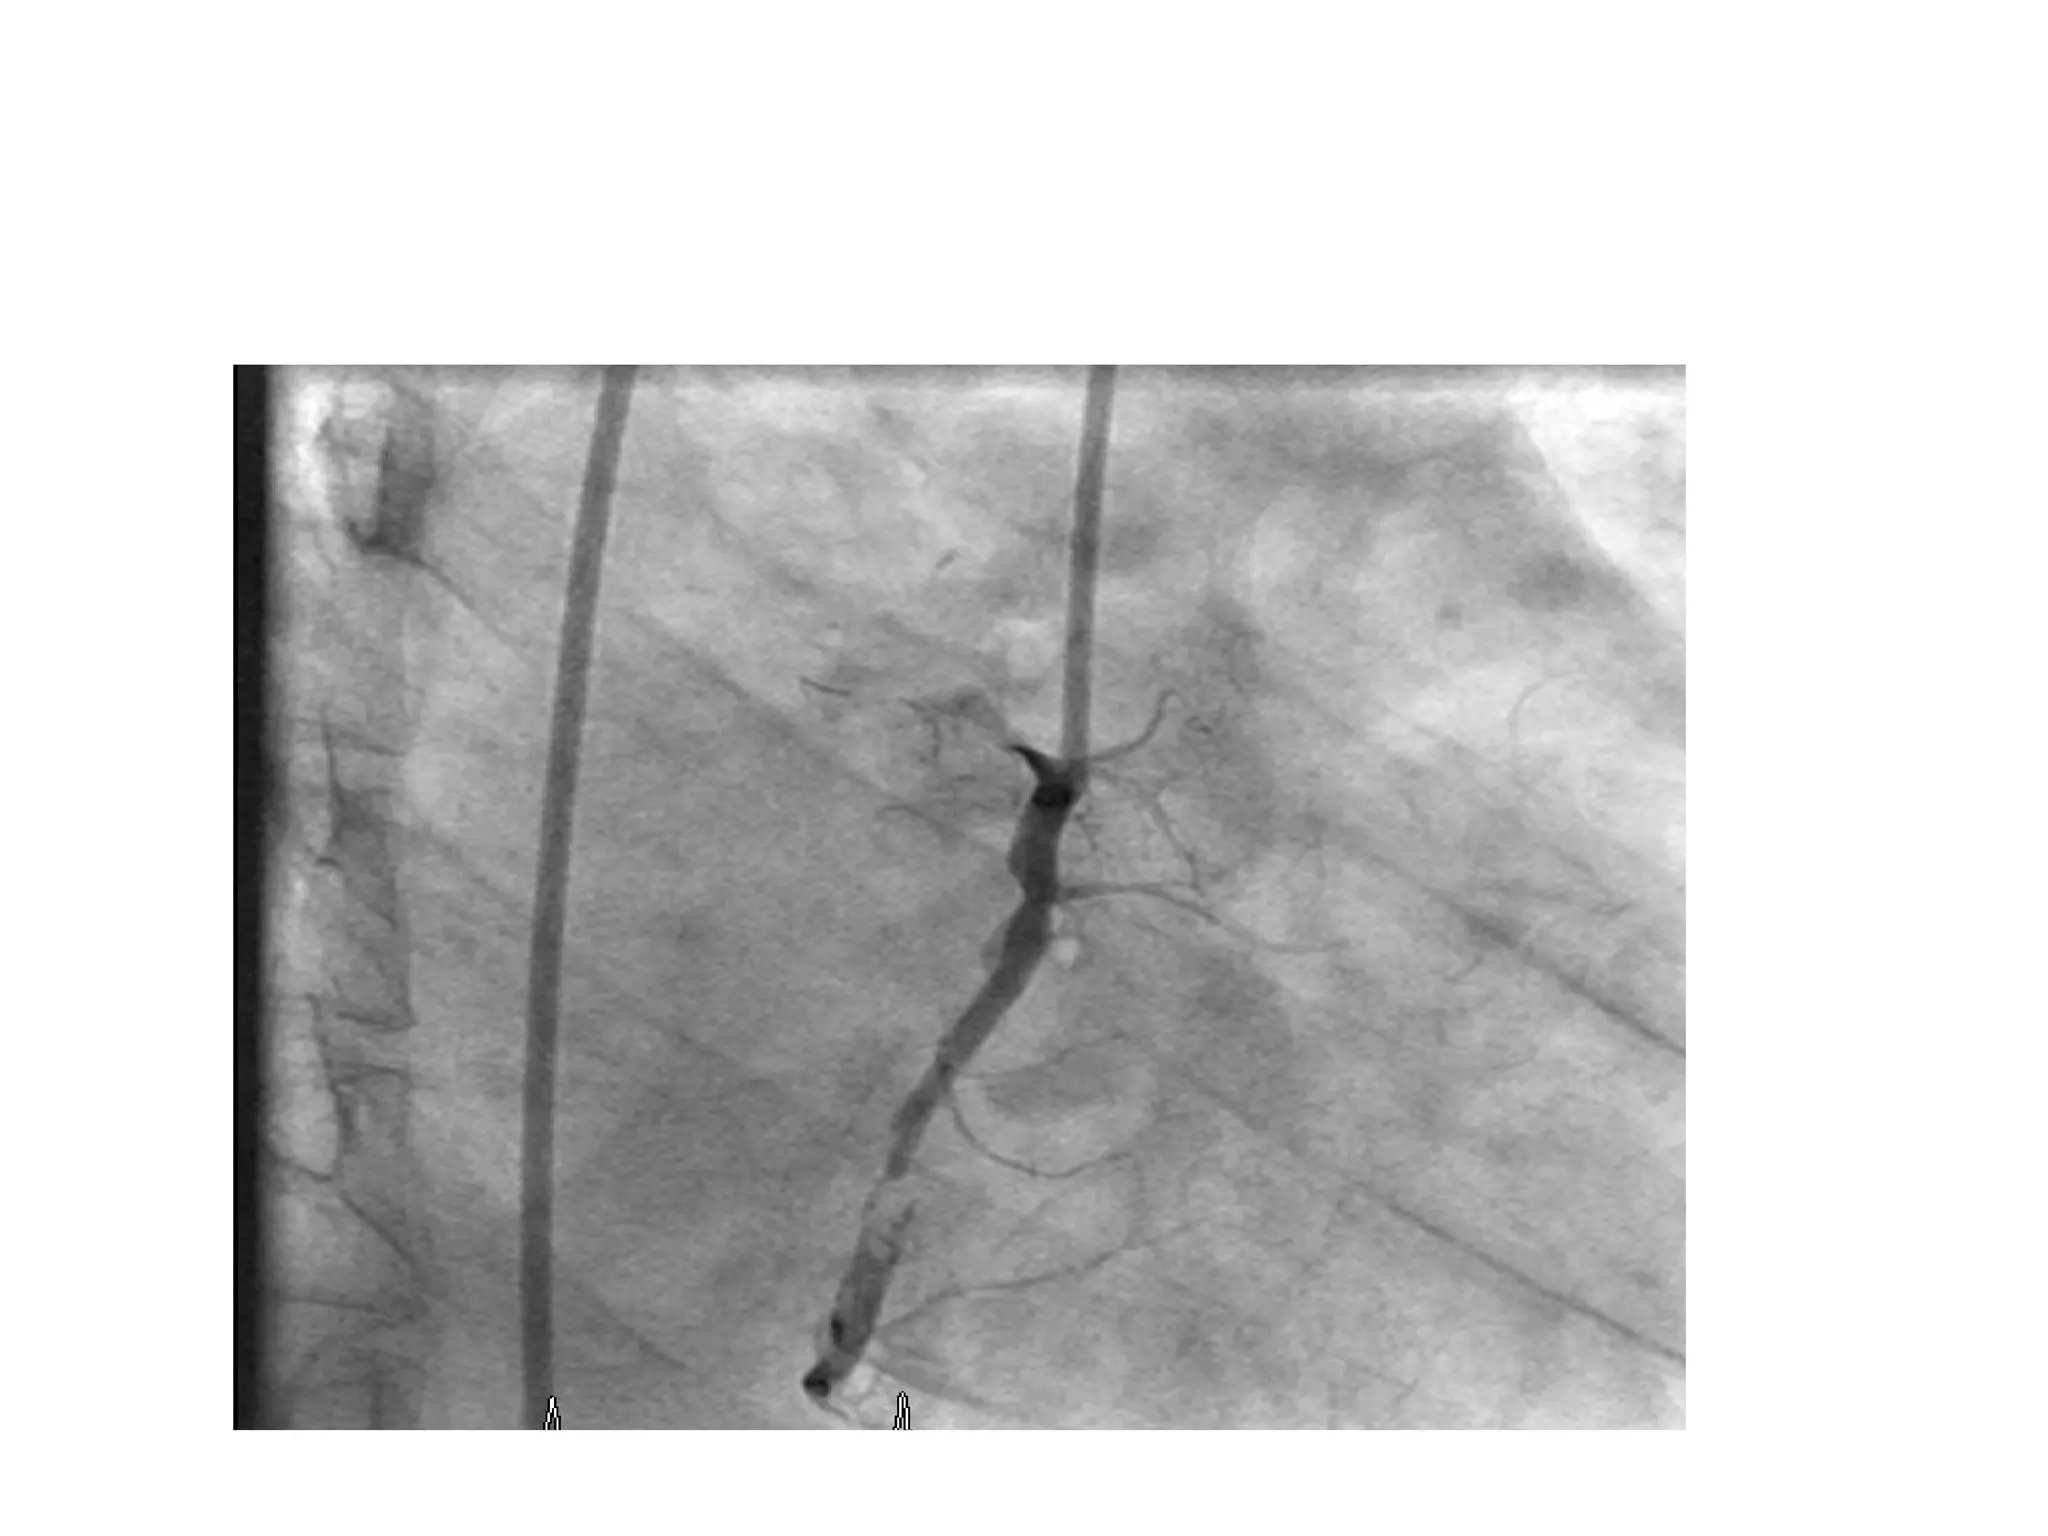

A 43-year-old man presented with chest pain and was diagnosed with an acute inferior ST elevation myocardial infarction with evidence of right coronary artery occlusion but no right ventricular involvement; he underwent primary percutaneous coronary intervention of the mid right coronary artery, which had a clot. The same patient had a complex lesion in the left anterior descending artery and its diagonals requiring staged percutaneous coronary intervention. A 55-year-old woman with diabetes and chest pain was found to have severe reversible ischemia in the territories of the left anterior descending artery and right coronary artery on nuclear stress testing, with normal circumflex artery area; coronary angiography revealed a critical proximal lesion in the left anterior descending artery.